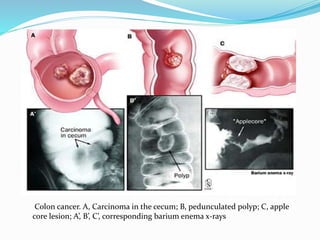

This document discusses colorectal polyps. It defines polyps and describes their types, including neoplastic and non-neoplastic polyps. It discusses adenomatous polyps in depth, noting their malignant potential increases with size over 1cm and villous architecture. Radiological diagnostic methods for polyps including single and double contrast barium enema and CT colonography are explained. The document provides an overview of polyp pathogenesis and genetic syndromes like FAP that increase cancer risk.